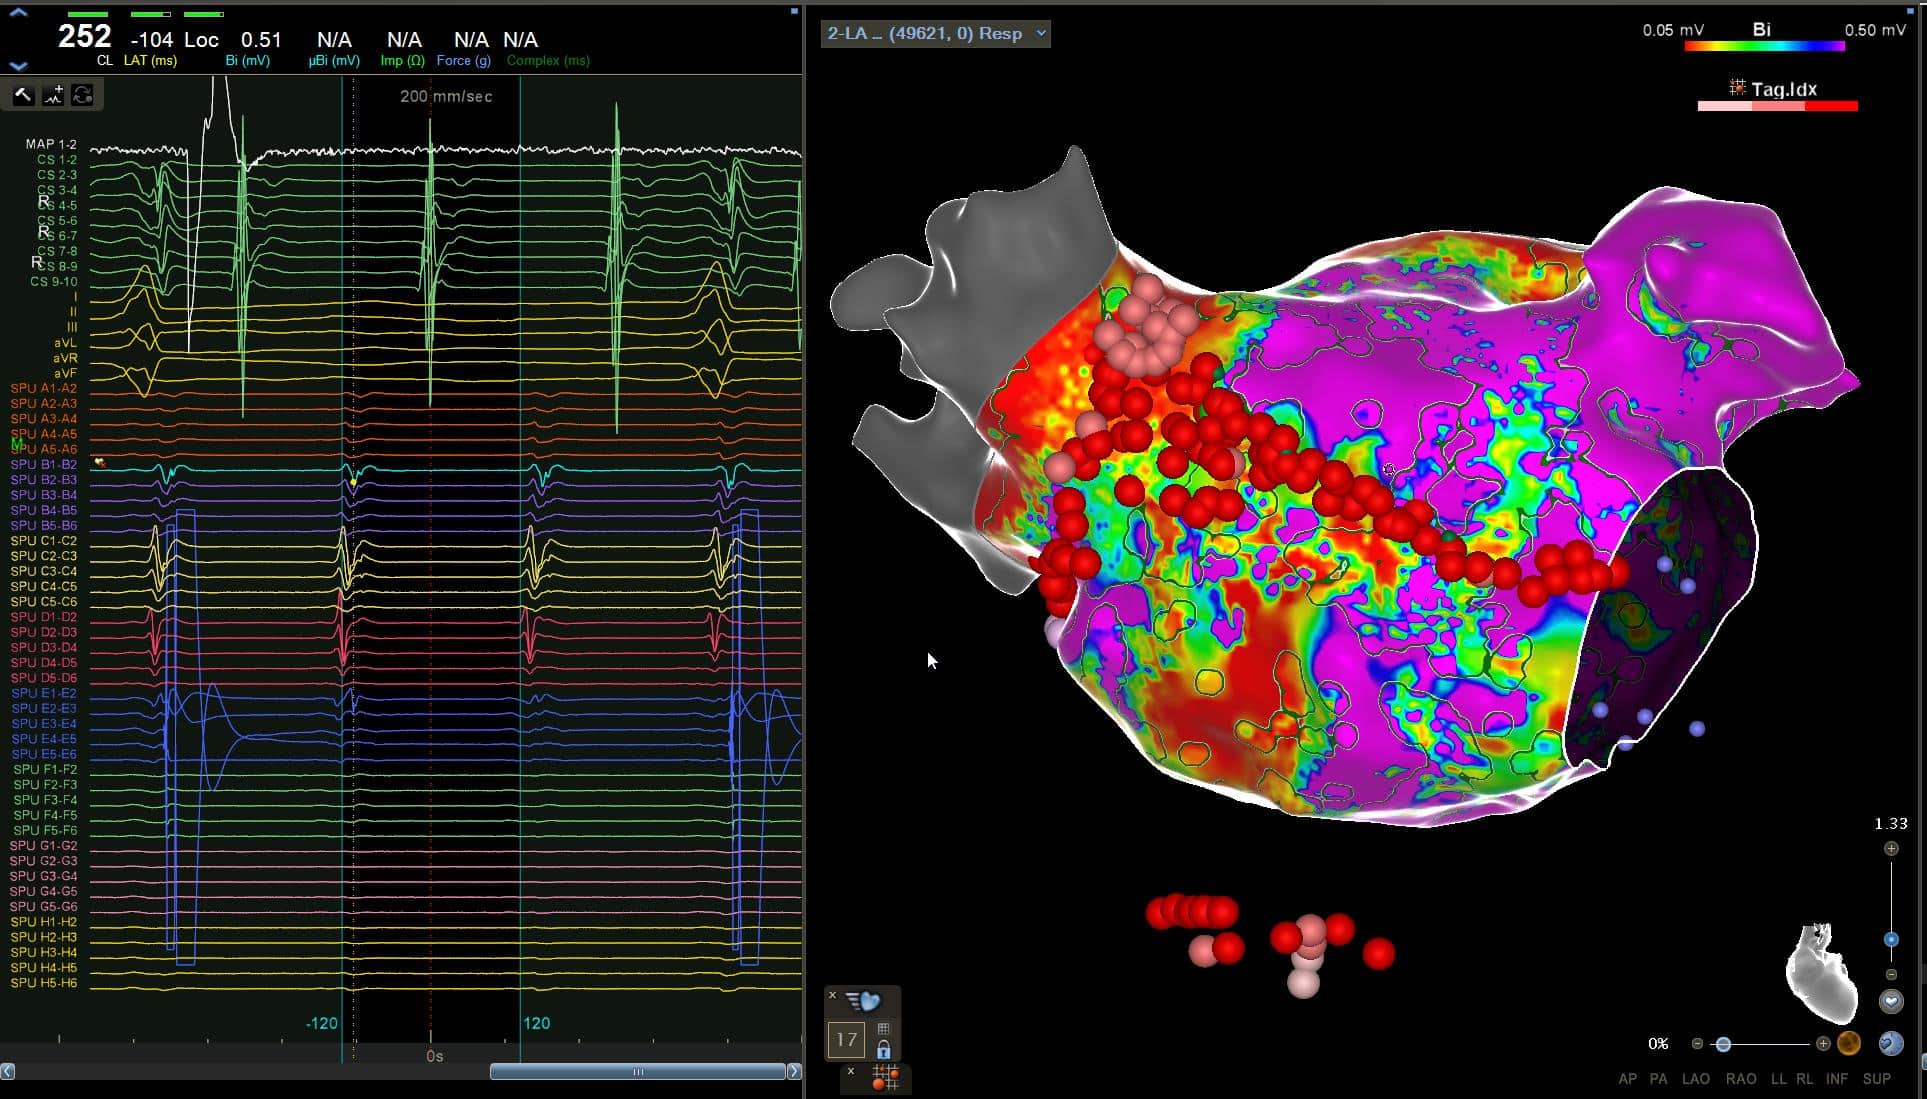

AF Pathophysiology, denovo pulmonary vein isolation, redo AF ablations & a deeper dive into the evidence, controversies & practicalities of ablating non-pulmonary...

Focal AT Activation Mapping

Open Window Mapping

Components of a VT Circuit